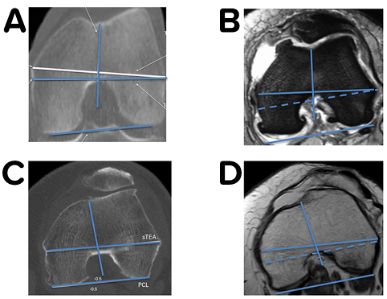

Without knowing all the details of this complex 3-D biomechanics of the patellofemoral joint, Insall has recommended to realign the prosthesis to the extensor mechanism during TKA surgery already 40 years ago. He introduced the tibia tubercle axis (TTA) for rotational alignment (Fig 21) which brings the TT under the trochlea from extension until deep flexion in all cases [1]. Most surgeons follow this simple technique but never thought about the wide variation of the TT to the proximal tibia anatomy. During the last decade several studies using 3-D imaging have shown that proximal tibia axial deformity is common in TKA patients and the TT position to the proximal tibia anatomy is very variable [22,30,48]--. Furthermore, it could be demonstrated that in varus knees external torsional deformities showed a clear correlation to the severity of the frontal malalignment [52]. The most commonly used measurement technique for knees with TKA is the anterior tibia tubercle angle (ATTA), which measures the angle between two lines (Fig 1 B and C) [4,30].

Due to the wide variability of the TT location some surgeons prefer the functional alignment philosophy and ignore the TT as a landmark [22,48]. Most of them use 3-D planning on CT or MRI, computer navigation or the floating technique to align the tibia perpendicular to the TEA of the femur in extension [53]. During surgery it is difficult to project the TEA onto the tibial plateau and therefore many different lines and landmarks are described to solve this problem. Akagi first described a line perpendicular to the TEA which ends at the medial border of the TT [54]. In several studies comparing different tibia lines and axis this Akagi line represented the most reliable bony landmark to align the tibia component perpendicular to the TEA and is therefore used by many surgeons [3]. Nevertheless, all these published lines show a wide variability and range due the common proximal axial plane deformity of the tibia [22,30,48]. Furthermore, the Akagi line is misleading, since he used natural knees with screw home mechanism in his study. This is why the Akagi line recommends the medial third of the tibia tubercle and not the mid to medial third, described by Insall [55]. The “curve on curve” technique represents the second reliable landmark to align the tibia component perpendicular to the TEA and is used by many surgeons in combination with the Akagi line [56].

For every TKA we mark the tibia tubercle axis (TTA) of Insall and compare it with the anatomical centre of the proximal tibia using the mid-sulcus line (Fig 22 A and B).

The TTA should be max 5 mm or 25° external rotated to the mid-sulcus line in normal knees, and any proximal axial deformity of the tibia can be easily identified. For the tibia rotational alignment, we use two landmarks only. The TTA of Insall (functional landmark) and the “curve on curve” technique (anatomical landmark). When performing a medial pivoting knee, we combine the “floating technique” with the two landmarks to find the best rotational compromise to allow a lateral rollback in flexion without producing a patella lateralization in extension .